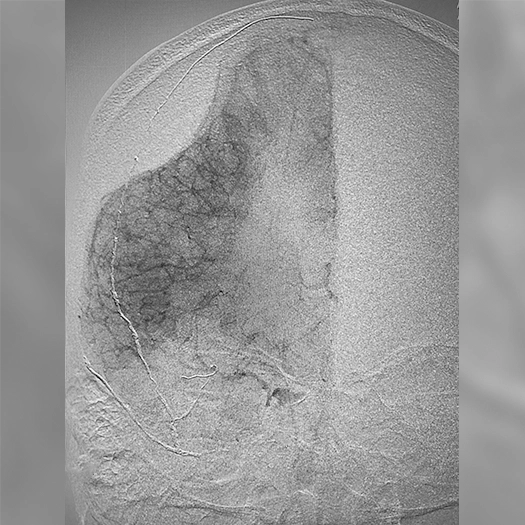

angiogram of embolization coils placed in a vessel

Proximal vessel sacrifice of LICA/LECA using POD400, PAC400, and PC400. A total of 877 cm of coil delivered by ACCESS25

Vessel Sacrifice

• POD400 + PAC400 for vessel sacrifice

• .020″ platform offered high volume and flexibility in case

• POD400 created a backstop, filled with PAC400

• BMX81 designed for stable vascular access